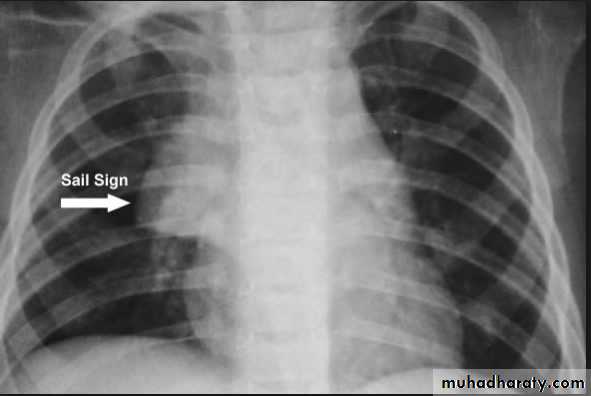

Thymoma.

A chest x-ray (A) reveals an unusual contour over the left hilum (arrows). That the hilum is not obscured (no silhouette sign) indicates that the mass must either be in front of or behind the hilum. A computed tomography scan (B) reveals a soft tissue mass (arrow) just to the left of the aorta. This is the most common location of a thymoma.Mediastinal teratoma. A chest x-ray (A) shows a large upper right mediastinal mass (arrows), but no specific internal structure is apparent. A computed tomography scan (B) reveals that the mass contains multiple types of tissue elements including fat (dark), soft tissue (gray), and calcium (white). This is essentially diagnostic of a teratoma.